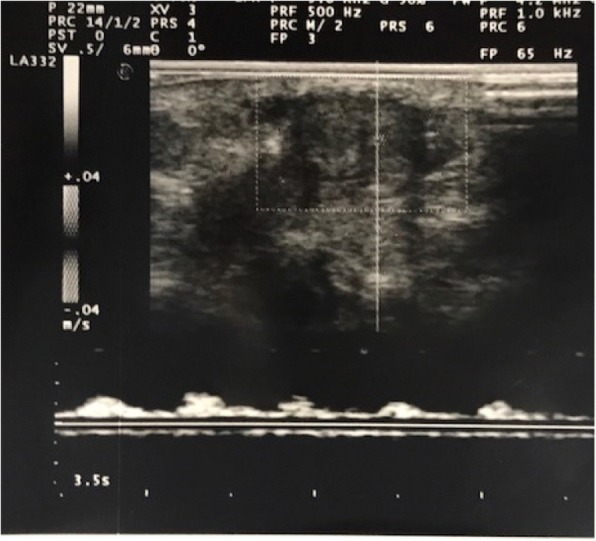

Our baby was born at 40 weeks and 2 days with a birth weight of 3380 g, to a 37-year-old healthy woman with an uneventful pregnancy. A Caesarean section was performed because of foetal distress and the Apgar score was 5, 7 and 7 at 1, 5 and 10 min respectively. The infant required cardio-pulmonary resuscitation at the first minute and than he was transferred to our Neonatal Intensive Care Unit. He was admitted to our Department with a diagnosis of moderate hypoxic ischemic encephalopathy. Consequently he was submitted to hypothermia treatment at 4 h and immediately he showed a persistent painless penile erection (Fig. 1) without discolouration of the scrotum or penis, and with bilaterally palpable testicles. An Ultrasonography examination of the arteries and the veins of the penis (Fig. 2), and laboratory findings (blood count and biochemical parameters) were normal. Once confirmed non-ischemic priapism, conservative treatment was chosen. Detumescence occurred after 4 h. The newborn continued to have intermittent erections with minimal stimulation for three days. At discharge physical examination was normal. On follow-up at 15 days and at one month, the patient had a normal physical examination and the mother reported normal erections.

Fig. 2.

Color Doppler ultraonography Normal arterial flow on Colour Doppler Ultrasonography (CDU) of the penis in our newborn with priapism